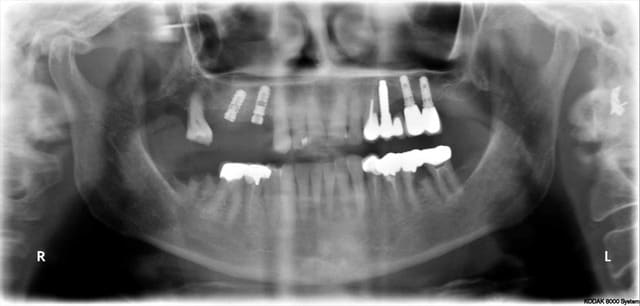

Ah oui, j'adore la 36 sur la pano !

"Ah oui, j'adore la 36 sur la pano !"

et que dire de 18 et 47!!